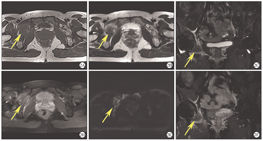

这11例UEC/DEC患者占本院同时期确诊为子宫内膜癌患者的1.8%(11/629),其一般临床、实验室、影像学及病理学检查结果如下。①临床资料:确诊时11例UEC/DEC患者的中位年龄为50岁(43~65岁),中位BMI为24.7 kg/m2;绝经后患者为8例,围绝经期为1例;有糖尿病者为2例;3代以内直系亲属有肿瘤史者为5例;手术方式为经腹者为5例,经腹腔镜者为6例;FIGO临床分期为早期(Ⅰ~Ⅱ期)者为6例,晚期(Ⅲ~Ⅳ期)者为5例。5例FIGO Ⅲ~Ⅳ者中,1例(No.3)伴腹主动脉旁淋巴结转移,2例(No.7、9)伴子宫外盆腔扩散,1例(No.2)同时伴卵巢和腹主动脉旁淋巴结转移,1例(No.8)伴远处髋臼转移。②主要临床表现:阴道不规则流血者为9例,下腹胀痛者为2例。③实验室检查结果:4例(No.2~3、9~10)患者血清肿瘤标志物糖类抗原(carbohydrate antigen,CA)125,人附睾蛋白(human epididymis protein,HE)4水平升高。④影像学检查结果:11例UEC/DEC患者的超声检查提示子宫内膜增厚或宫腔内有不均质回声团(图1A);MRI结果提示子宫内膜不规则增厚或宫腔内占位,呈等T1、稍长T2信号影,弥散加权序列上呈明显的高信号,表观弥散系数图呈低信号,增强扫描可见病灶强化(图1B,图1C,图1D,图1E,图1F,图1G)。1例(No.8)患者初诊时,MRI检查见右侧髋臼下缘不规则斑片状等T1、短T2信号影,DWI序列呈高信号,增强扫描见不均质强化,伴周围软组织肿胀(图2),经皮右侧髋臼穿刺病理学检查结果证实为DEC的未分化组分(undifferentiated components,UC)转移至髋臼。⑤术前组织病理学检查结果:10例(No.1、3~11)患者术前行子宫内膜活组织病理学检查,2例(No.7~8)确诊为DEC,2例(No.1、3)为子宫内膜腺癌,5例(No.4~6、10~11)为低分化子宫内膜癌,1例(No.9)为子宫内膜息肉,1例(No.2)未行子宫内膜活组织病理学检查。⑥术后病理学检查结果:3例(No.3~4、11)为UEC,8例(No.1~2、5~10)UC合并低级别子宫内膜样癌成分,3例(No.1、3、6)UC合并高级别子宫内膜样癌成分,其中1例(No.3)同时还合并高级别浆液性癌成分;肿瘤最大直径≤2 cm为2例(No.1~2),>2 cm为9例(No.3~11),其中1例DEC患者(No.8)子宫切除后剖视可见宫腔内病灶大小约为2.2 cm×1.8 cm×1.2 cm,累及子宫壁>1/2肌壁全层(图1H);肌层浸润深度<1/2为7例(No.2~5、7、10~11),≥1/2为4例(No.1、6、8~9);11例患者均无盆腔淋巴结转移;腹主动脉旁淋巴结转移为2例(No.2~3),淋巴脉管间隙浸润为5例(No.4、6、8~10)。

注:DEC为去分化子宫内膜癌